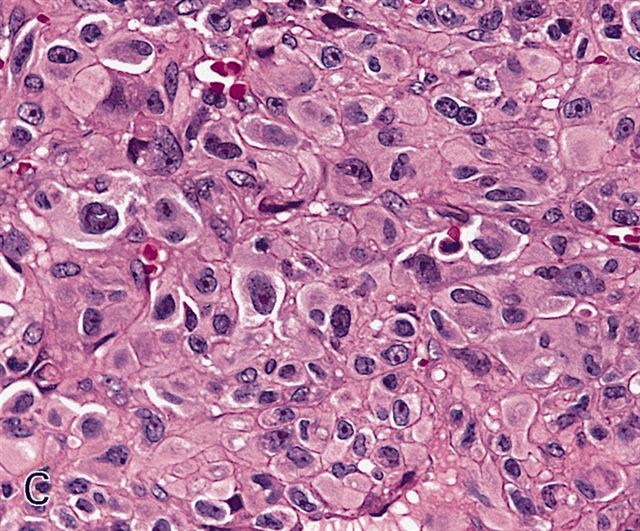

Microscopic (histologic) description

- Sheets of large, atypical and frequently multinucleated polygonal, spindled or rhabdoid eosinophilic cells (Am J Surg Pathol 2009;33:1850)

- Cross striations are seldom detected

Microscopic (histologic) images